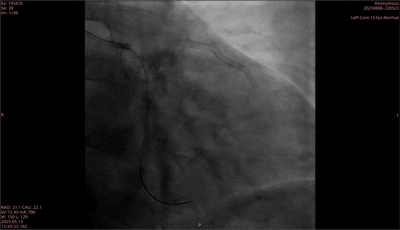

■ 手术治疗

手术过程中,首先于前降支植入2枚药物洗脱支架,重复造影显示狭窄解除。随后,使用2.0mm×15mm规格的预扩球囊对回旋支远段进行预扩张,扩张后直径狭窄程度为25%,血流TIMI 3级,但病变处在预扩后出现B型夹层。后续采用2.0mm×30mm的矩正医疗冠状动脉血管重塑导管,以6atm压力扩张血管,并同步启动激光治疗。最终,术后造影结果显示,狭窄处扩张效果良好,残余狭窄20%,且原夹层消失,血流TIMI 3级,手术圆满完成。

术后